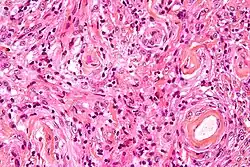

- A woven architectural pattern

- Psammoma bodies (spheroid calcifications)

- Syncytial cells (having indistinct cell membranes) with eosinophilic (pink) cytoplasms

- Round uniform nuclei

- Whorls (concentric cell arrangements)[16]

Meningiomas arise from arachnoidal cap cells,[17] most of which are near the vicinity of the venous sinuses, and this is the site of greatest prevalence for meningioma formation. Some subtypes may arise from the pial cap cells that migrate during the development together with blood vessels into the brain parenchyma.[18] They most frequently are attached to the dura over the superior parasagittal surface of frontal and parietal lobes, along the sphenoid ridge, in the olfactory grooves, the Sylvian region, superior cerebellum along the falx cerebri, cerebellopontine angle, and the spinal cord. The tumor is usually gray, well-circumscribed, and takes on the form of the space it occupies. They usually are dome-shaped, with the base lying on the dura.

Histologically, meningioma cells are relatively uniform, with a tendency to encircle one another, forming whorls and psammoma bodies (laminated calcific concretions).[19] As such, they also have a tendency to calcify and are highly vascularized.